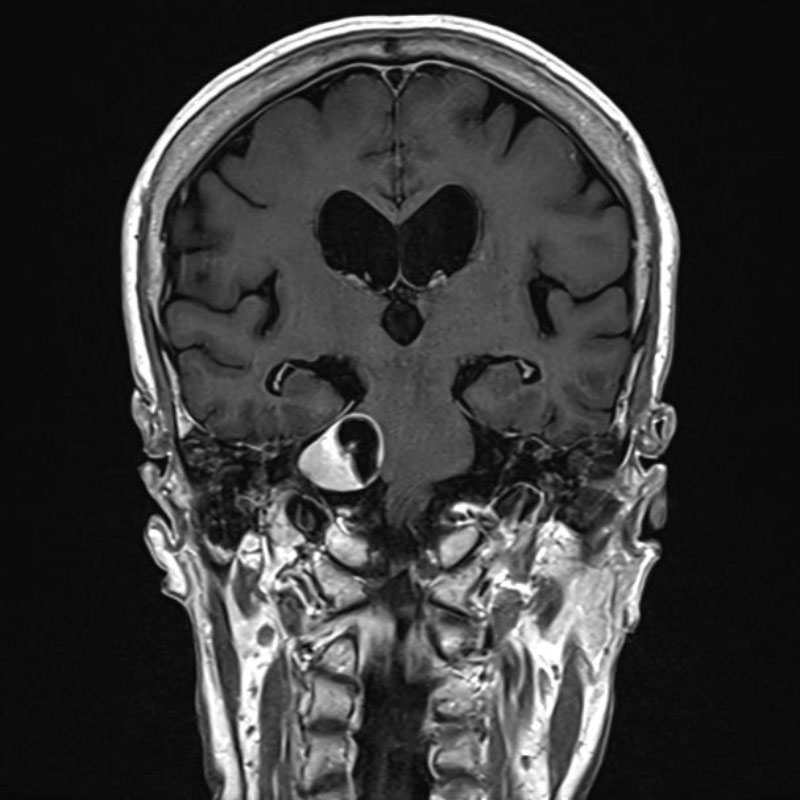

696

'25年11月

70代

眼窩腫瘍

頭蓋内腫瘍摘出術

No.’25_98 手術前1

No.’25_98 手術前2